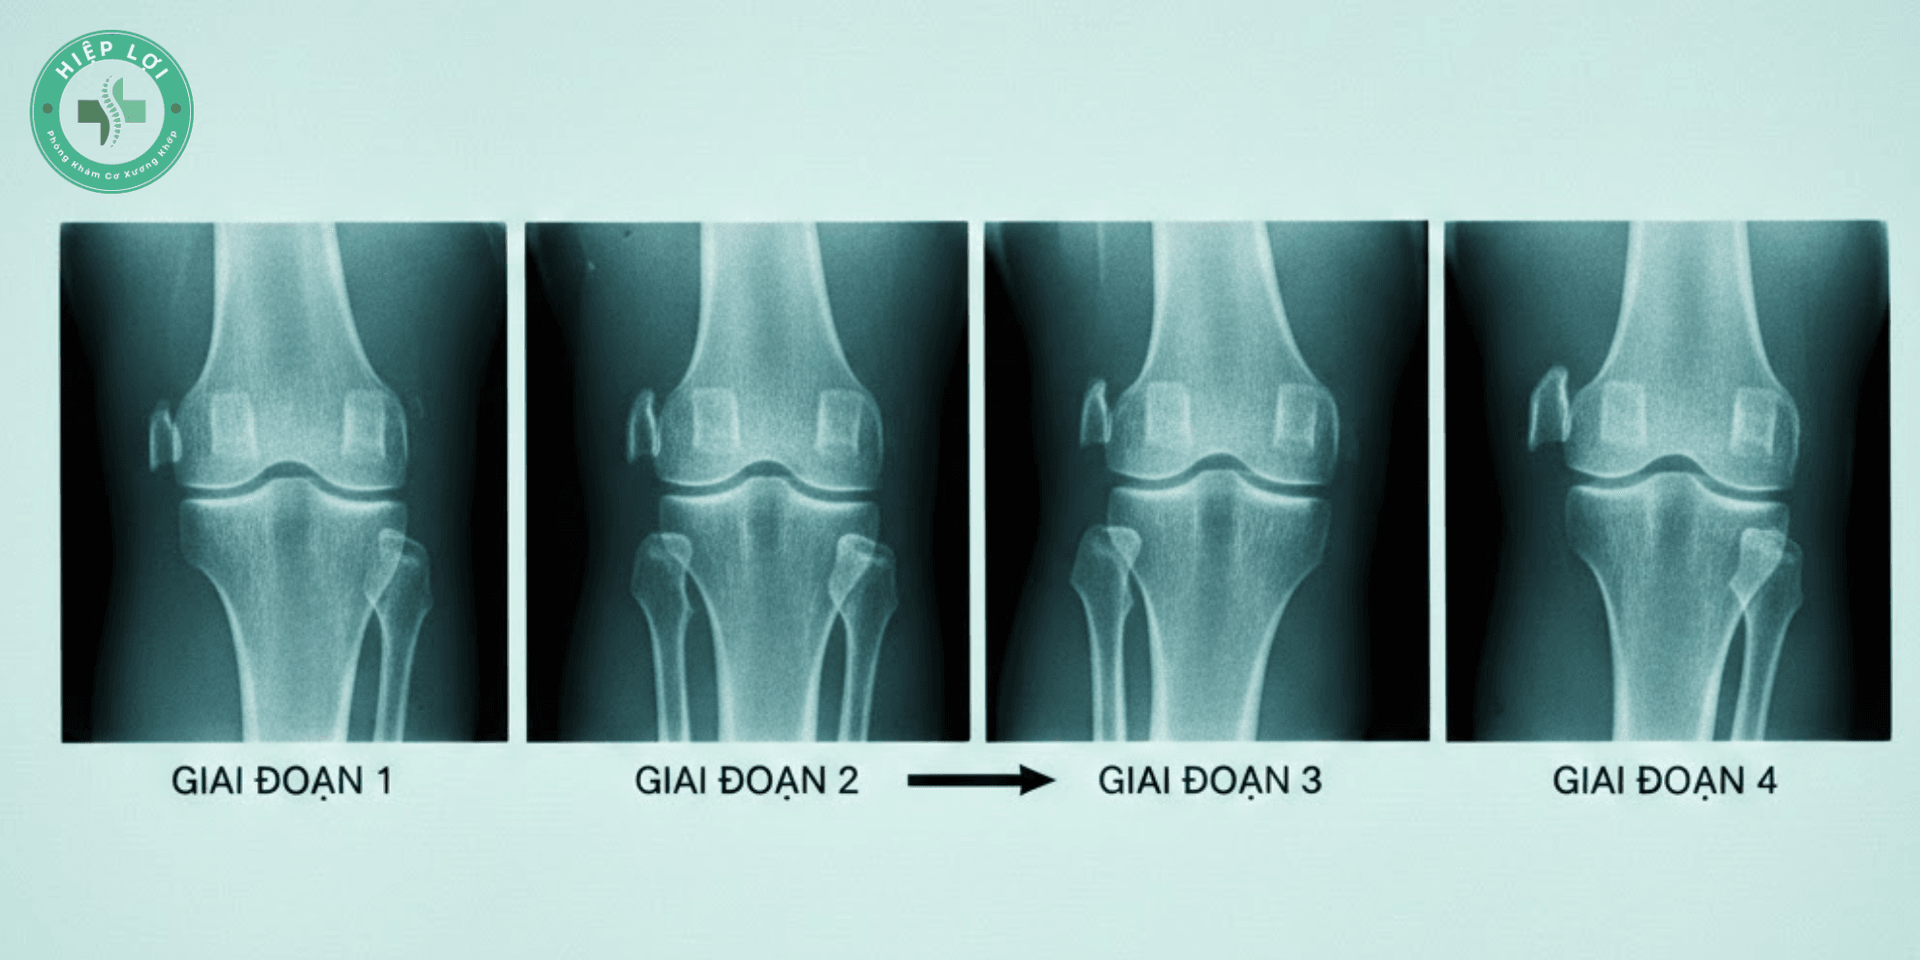

Nhận diện 4 giai đoạn tiến triển - Bạn đang ở đâu?

Việc hiểu mình đang ở giai đoạn nào giúp bác sĩ Hiệp Lợi đưa ra phác đồ phù hợp nhất:

Giai đoạn 1: Giai đoạn "Cảnh báo"

- Khớp gối chưa có tổn thương rõ trên X-quang.

- Cảm giác: Thỉnh thoảng thấy mỏi gối khi đi bộ xa hoặc đứng lâu. Cơn đau qua nhanh sau khi nghỉ ngơi.

Giai đoạn 2: Giai đoạn "Bắt đầu bào mòn"

- Khe khớp bắt đầu hẹp nhẹ, xuất hiện các mấu gai xương nhỏ.

- Dấu hiệu: Nghe tiếng "lục cục" hoặc "lạo xạo" trong gối khi co duỗi. Đau rõ rệt khi leo cầu thang hoặc đứng lên từ ghế thấp.

Giai đoạn 3: Giai đoạn "Tổn thương rõ rệt"

- Khe khớp hẹp thấy rõ, gai xương to ra. Lớp sụn bị loét sâu chạm đến xương.

- Triệu chứng: Khớp thường xuyên bị sưng (tràn dịch). Cứng khớp buổi sáng kéo dài. Đi bộ khoảng 500m là phải dừng lại vì đau.

Giai đoạn 4: Giai đoạn "Cuối - Biến dạng"

- Sụn khớp gần như mất hoàn toàn, hai đầu xương chạm sát vào nhau.

- Hệ quả: Chân bị vòng kiềng, teo cơ đùi. Đau dữ dội kể cả khi nằm ngủ. Ở giai đoạn này, điều trị bảo tồn rất khó khăn, thường phải chỉ định thay khớp nhân tạo.

Hình ảnh phim X-quang thực tế của 4 giai đoạn